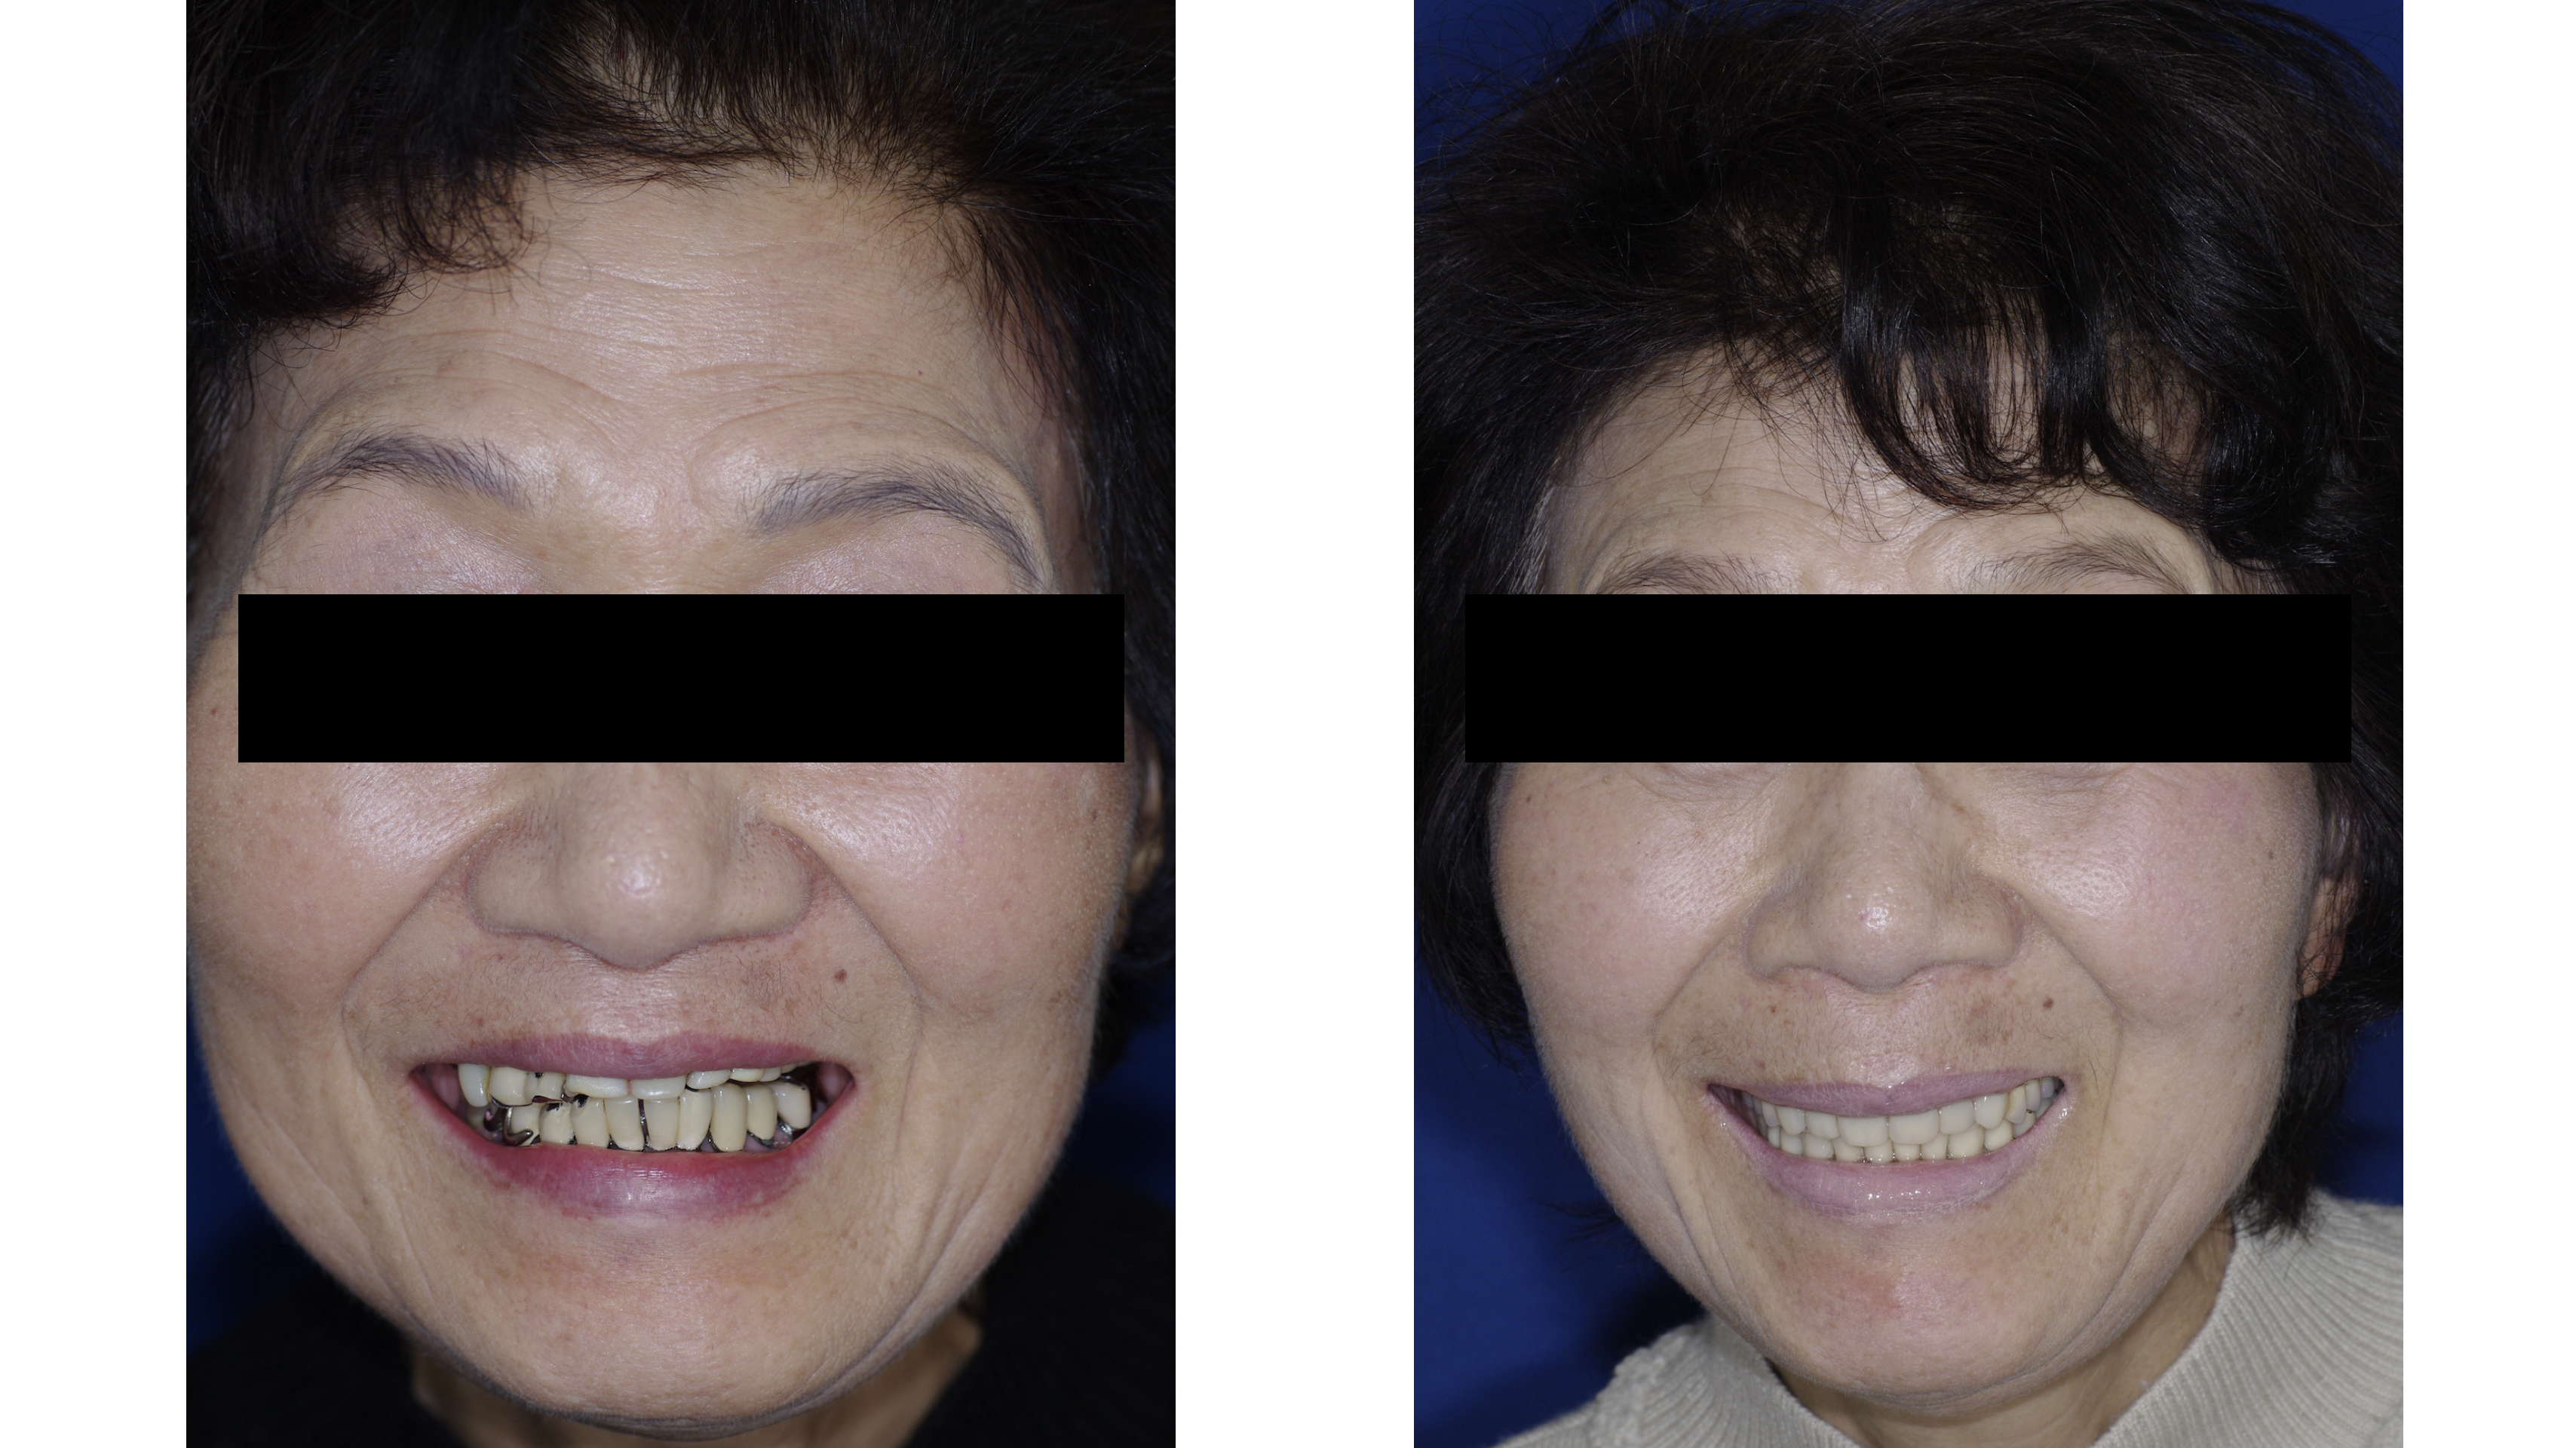

口元は美しく ごきげんに

機能が改善されると審美性も改善されます。

美しい口元で会話が弾みます。

健康寿命を伸ばす強力な要素の1つは社会性です。

素敵な仲間と楽しい時間を!

美しい口元で会話が弾みます。

健康寿命を伸ばす強力な要素の1つは社会性です。

素敵な仲間と楽しい時間を!